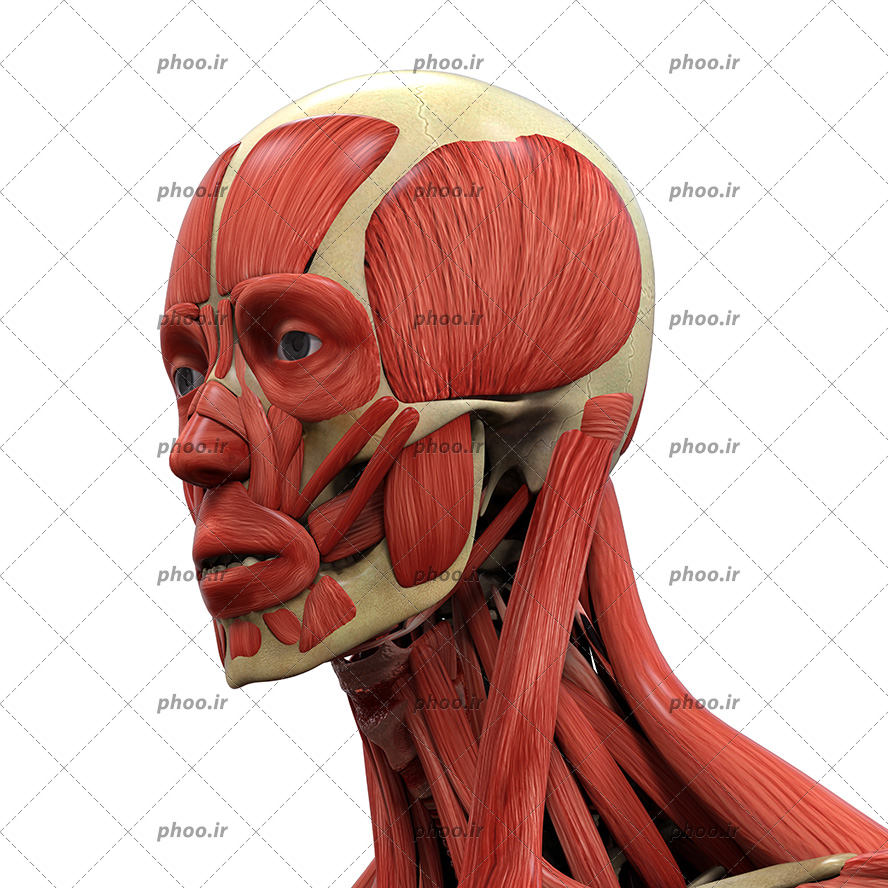

اسکلت جمجمه و گردن انسان ستون فقرات آناتومی اسکلت جمجمه و گردن انسان ستون فقرات آناتومی تصویر با کیفیت را از لینک زیر می توانید دانلود کنید. ۱ مطلب با کلمه ی کلیدی عکس اسکلت بدن انسان با کیفیت ثبت شده است گالری نسیم جدید ترین و با کیفیت ترین عکس های مناسبتی. عکس با کیفیت آناتومی اسکلت بدن انسان و درد و دیسک در قسمت مهره های ستون فقرات کمر ویژه استفاده در امور تبلیغاتی و تجاری طراحی کاتالوگ بروشور و تراکت با موضوع بیمارستان ها و کلینیک ها و درمانگاه ها و مطب ها پزشکان و.